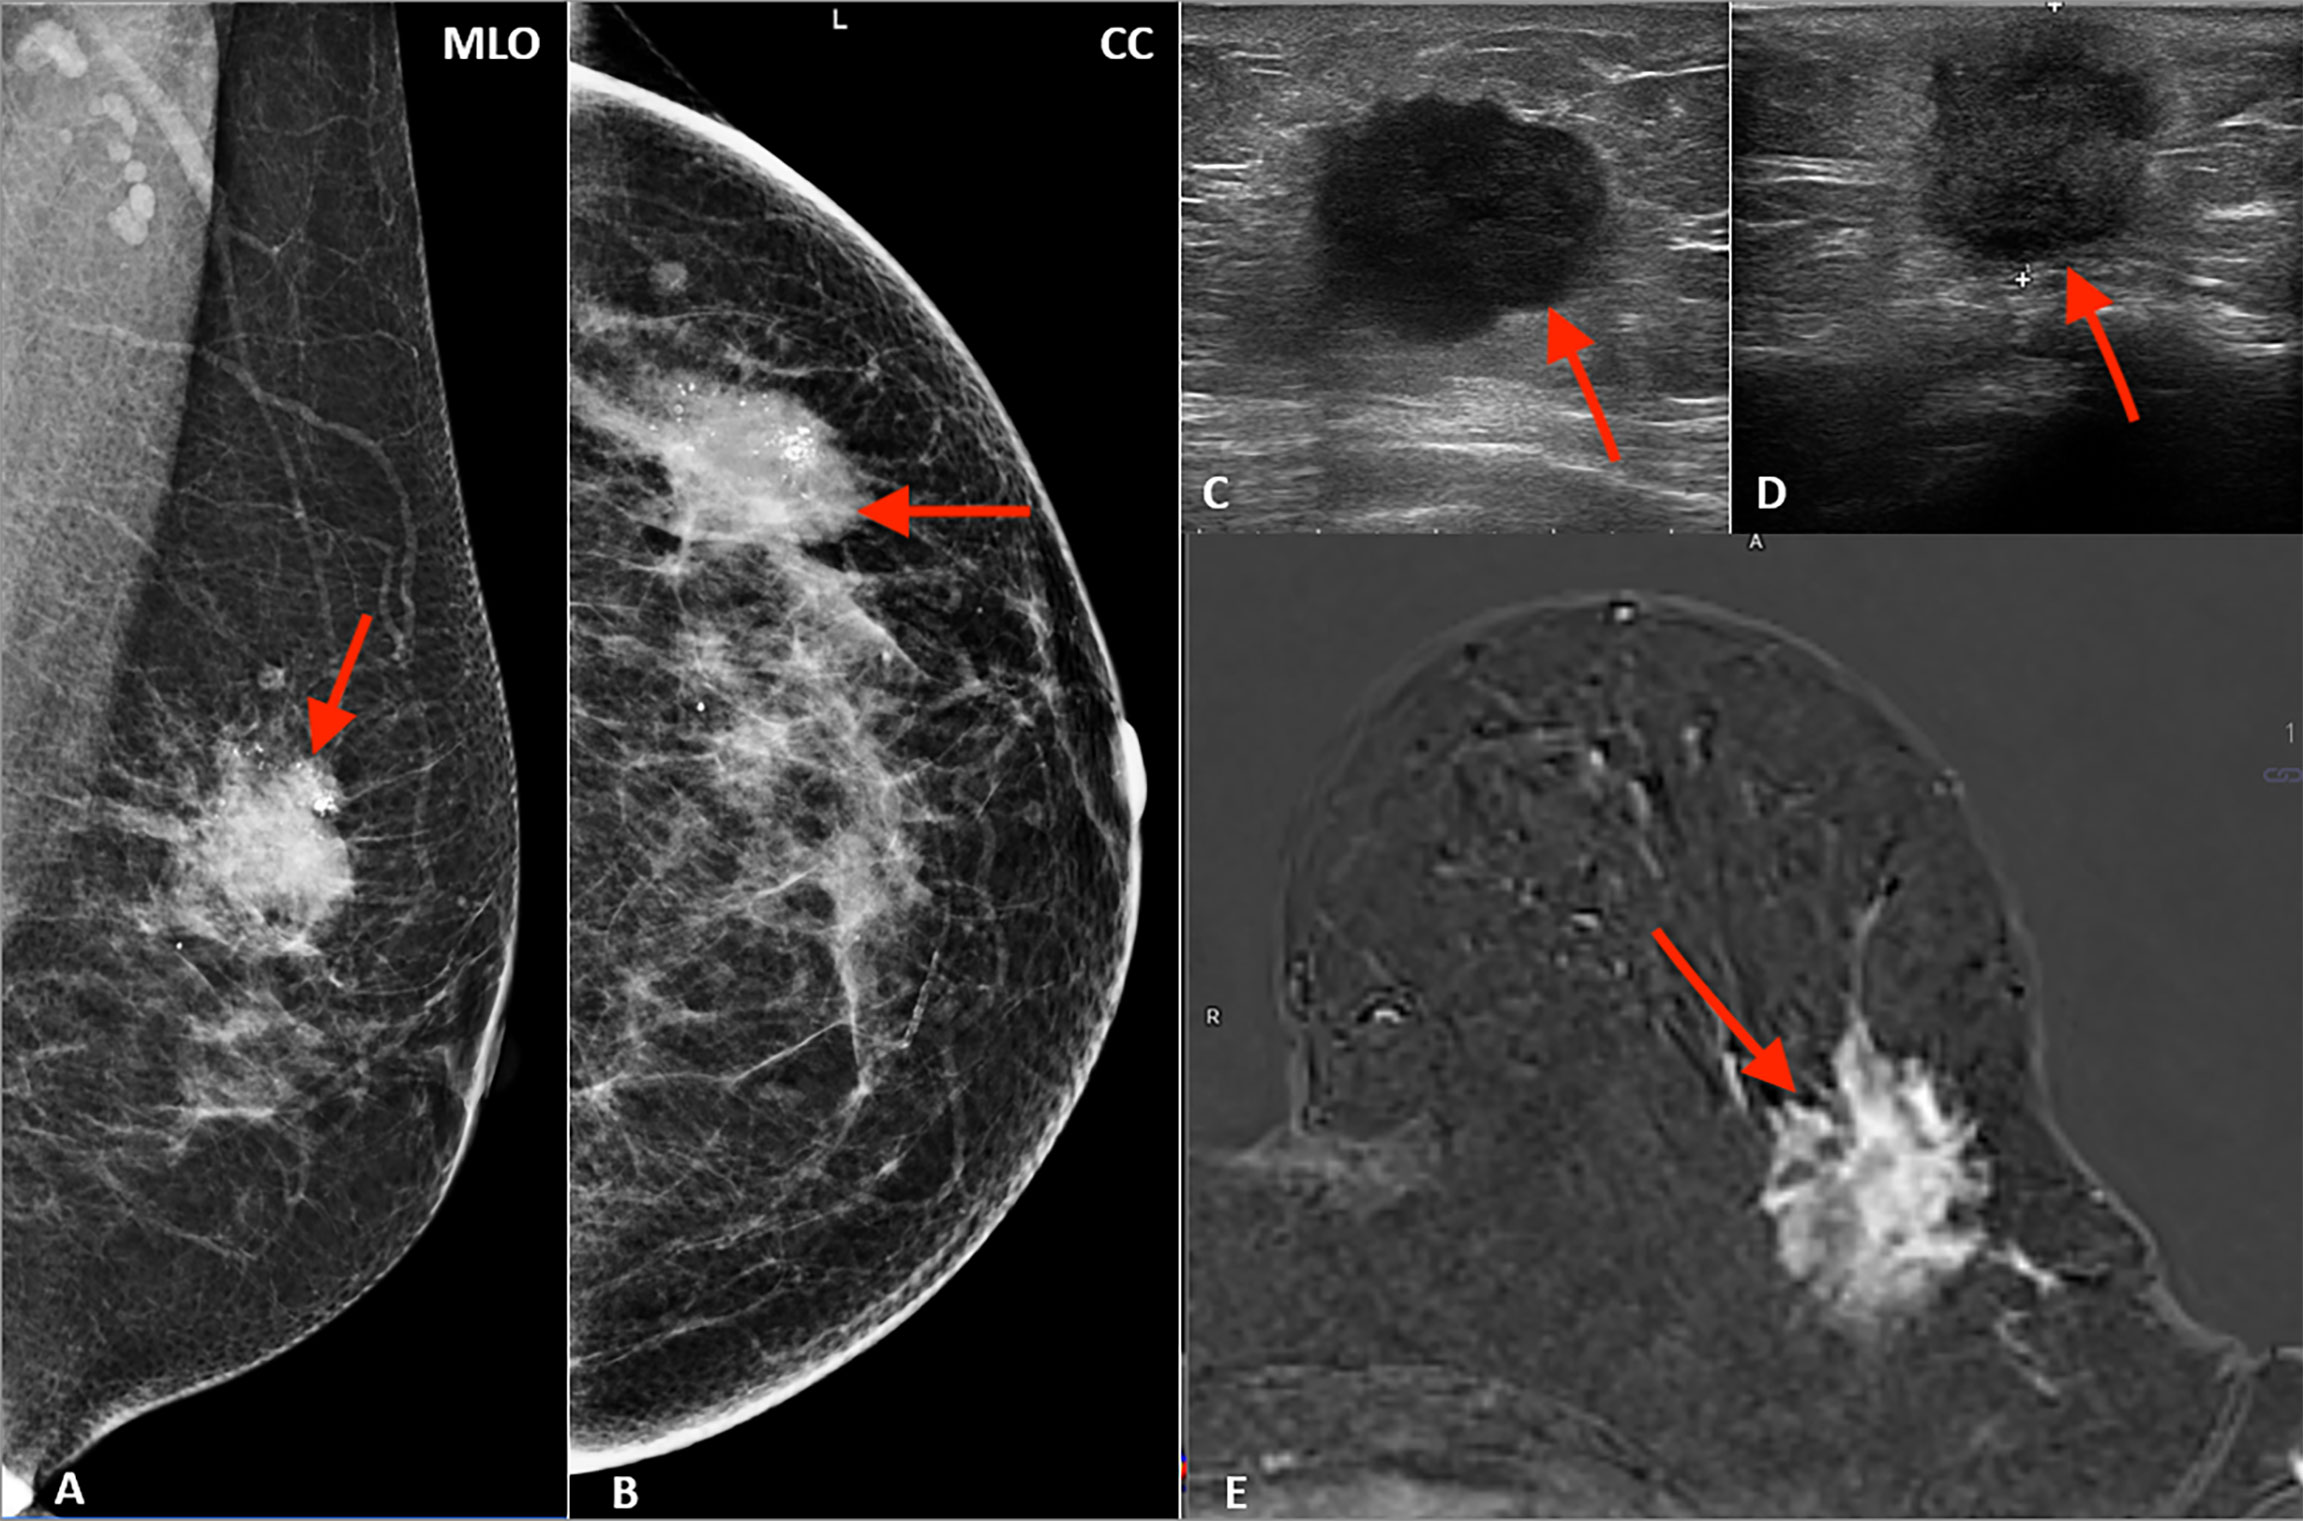

Ultrasound (USG) Both Breast Scan is a specialized imaging examination used to evaluate both breasts for any abnormalities or changes in breast tissue. This non-invasive procedure employs high-frequency sound waves to create detailed images of the breast tissue, including the mammary glands, ducts, and surrounding structures. By examining both breasts simultaneously, radiologists can compare any differences in breast tissue and identify any suspicious findings such as masses, cysts, or areas of increased vascularity. USG Both Breast Scan is commonly used as a supplementary imaging tool alongside mammography or as a primary screening method for women with dense breast tissue or those at higher risk for breast cancer. It plays a crucial role in early detection, diagnosis, and monitoring of breast conditions, ultimately contributing to better outcomes and management of breast health.

Ultrasound (USG) Single Breast Scan is a focused imaging procedure used to examine a specific breast for any abnormalities or changes in breast tissue. This non-invasive technique utilizes high-frequency sound waves to produce detailed images of the breast, including the mammary glands, ducts, and surrounding structures. By concentrating solely on one breast, radiologists can closely evaluate any identified masses, cysts, or areas of concern, aiding in the diagnosis and management of breast conditions such as tumors, cysts, or fibroadenomas. USG Single Breast Scan is often recommended when a specific area of interest is identified during a clinical breast examination or mammography, providing additional information to guide further evaluation or treatment decisions.